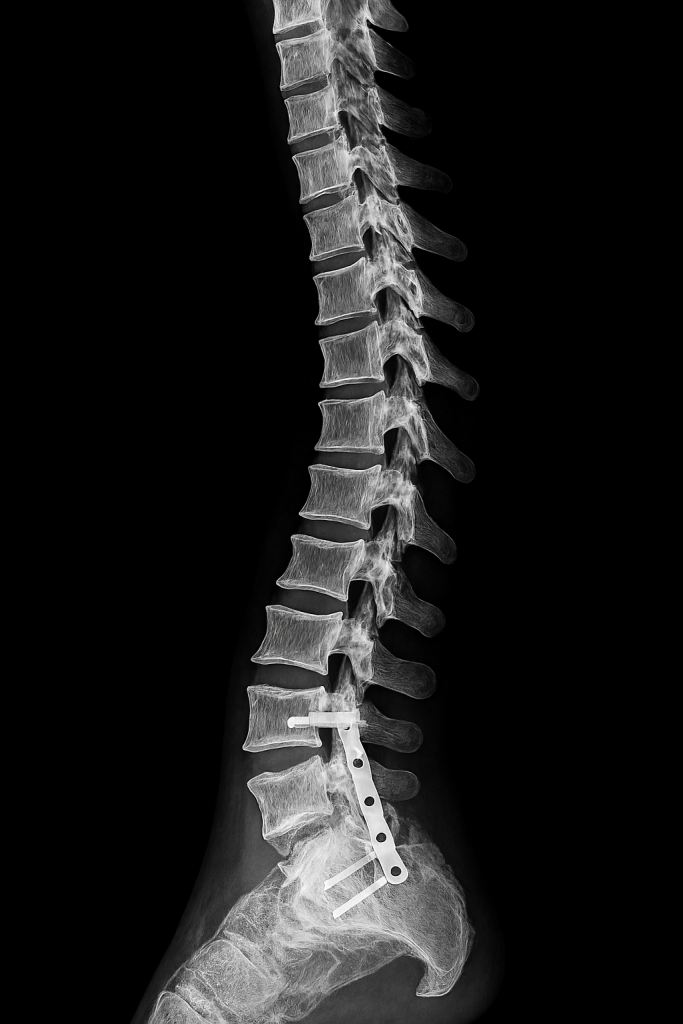

The Role of Elite Medical Support

Professional athletes have access to multidisciplinary medical teams that optimize every phase of recovery. Sports physicians, physiotherapists, orthopedic surgeons, and nutritionists collaborate to create individualized treatment plans. Diagnostic imaging such as MRI and ultrasound allows precise identification of tissue damage – guiding targeted interventions. Surgical techniques are often minimally invasive – reducing recovery time and preserving function. Rehabilitation protocols are progressive and evidence-based – incorporating strength, mobility, proprioception, and sport-specific drills. Manual therapy, dry needling, and neuromuscular re-education accelerate tissue remodeling. Nutrition is tailored to support healing – with emphasis on protein synthesis, anti-inflammatory compounds, and micronutrient balance. Recovery is monitored through biomarkers, performance metrics, and subjective feedback. This level of care is rarely available to the general public – creating a disparity in recovery outcomes.